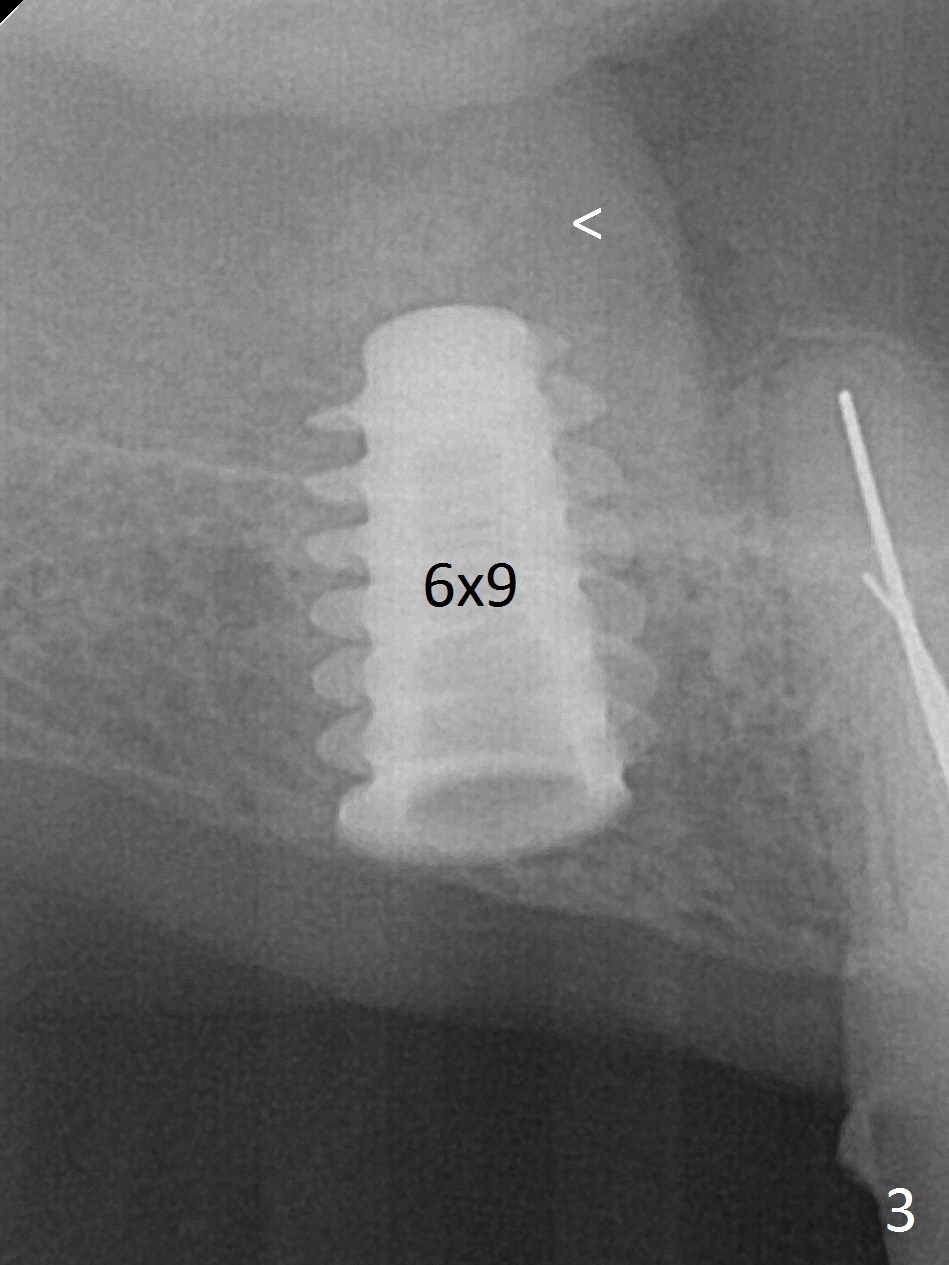

Since the ridge is wide at the site of #2, Magic Split is used for access (flapless) and bone expansion. The bone is so soft that there is no resistance until 4.3 mm Magic Expander is used for 9 mm (Fig.6). A 5 mm tap drill is stable (Fig.1), so are a 5.5x9 mm dummy implant (Fig.2) and a 6x9 mm IBS implant (Fig.3 (<: sinus lift)). In fact the distal thread is still supracrestal (Fig.4 (BW)). After additional 2 mm placement, the distal thread is subcrestal (Fig.5); the mesial margin of a 6.5x4(4) mm abutment is subgingival. A longer cuff (5 mm instead of 4 mm) is more favorable for future restoration. At present the abutment (Fig.7) as well as the tooth #3 with rugged surfaces is used to hold periodontal dressing in place. The abutment margin is completely subgingival 3 months postop (Fig.8 (white dashed line: gingival margin)). It appears that the implant is placed ~ 1 mm deeper than ideal (Fig.9). Diode laser is used for gingivectomy prior to impression. The abutment screw becomes loose 2 months post cementation. After retightening, occlusal equilibrium is conducted with 3 layers of articulating paper. Night guard is provided. The crown/abutment dislodges 1 year 2 months later. Since the gingiva is erythematous, a 6x7 mm healing abutment is placed (Fig.10). The implant seems to have been placed too deep and palatal. It appears that an abutment driver should be buried to prevent the screw re-loosening. Guided surgery should have been done.